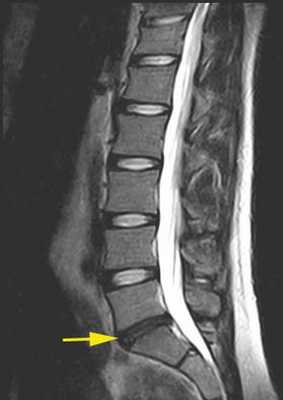

Поврежденный межпозвоночный диск с пониженным влагосодержанием. © joint-surgeon